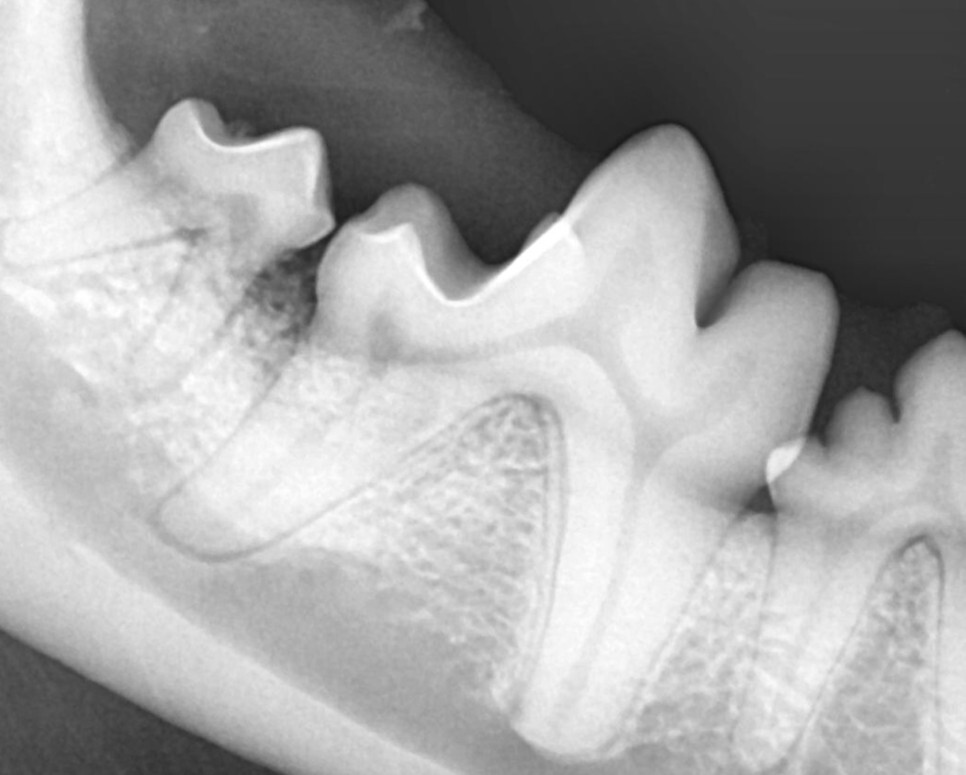

원인을 제거하였기 때문에 종양처럼 병변의 재발을 걱정할 필요는 없습니다. 하지만, 안타깝게도 반대쪽 치아에도 병변이 진행되고 있었습니다.

그나마 다행인 것이 반대쪽의 경우 진행 초기라

합성 뼈를 이식하는 것으로 치료를 할 수 있었습니다.